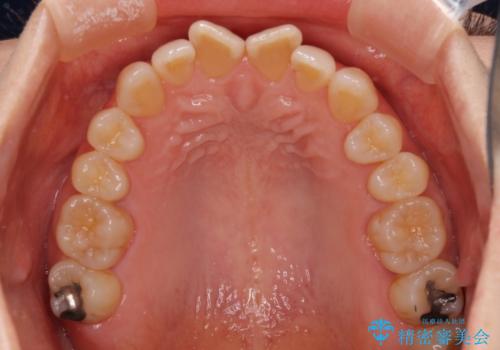

前歯の叢生と切端咬合 インビザラインによる矯正治療

- 前歯のデコボコを気にして来院された患者様です。

上下前歯の先端同士が接触する切端咬合であったため、上顎は歯列を拡大し、下顎はIPR(歯と歯の間を削る)により叢生を解消しながら歯列を小さくすることとしました。

治療前から歯肉退縮が認められ、矯正治療により悪化する可能性が考えられたため、無理のない歯の移動と頻繁な経過観察を行いました。

切端咬合はスムーズに解消され、前歯の負担を軽減させることができました。